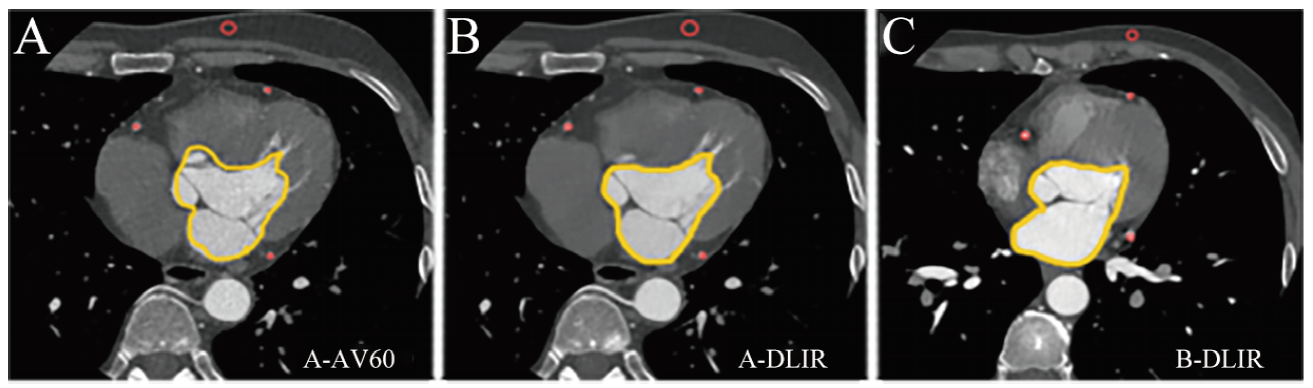

由2名具有4年工作经验的医学影像技师采用轮流监督的方法确保客观图像勾画准确,勾画原则:放大后轴面勾画、避开血管壁,取3次的平均,见图1。出现分歧时由具有17年工作经验的医学影像副主任技师实施最终勾画方案,读取数据。将ROI分别置于主动脉根(aortic root,AR)、左前降支(left anterior descending coronary artery,LAD)、左回旋支(left circumflex coronary artery,LCX)、右冠状动脉(right coronary artery,RCA)及同层胸前脂肪密度较均匀的区域内,记录各ROI的CT值及噪声值。参照测量层上下滚动测量3次,取3次平均值作为最终结果,计算各血管的信噪比(signal-to-noise ratio,SNR)和对比噪声比(contrast-to-noise ratio,CNR)。

图1 CCTA勾画示意图

注:A为A-AV60;B为A-DLIR;C为B-DLIR;红色为ROI测量RCA、LAD、LCX和胸前脂肪,黄色为勾画观察算法间噪声差异。

Figure 1 Schematic diagram of CCTA delineation